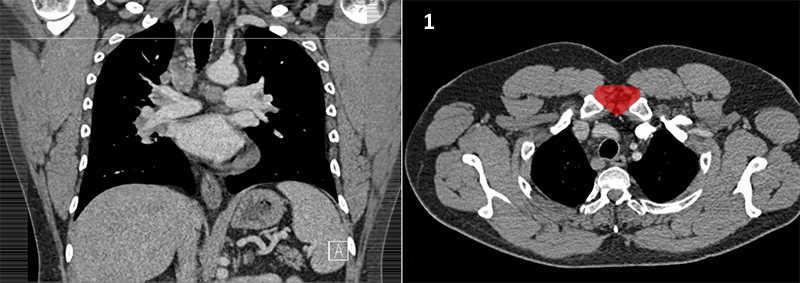

Nodal zones and stations according to the International Association for the Study of Lung Cancer (IASLC) node map.

Table (above): Nodal zones and stations according to the International Association for the Study of Lung Cancer (IASLC) node map. (Source: 1,2) *Depends on the side of the tumour.